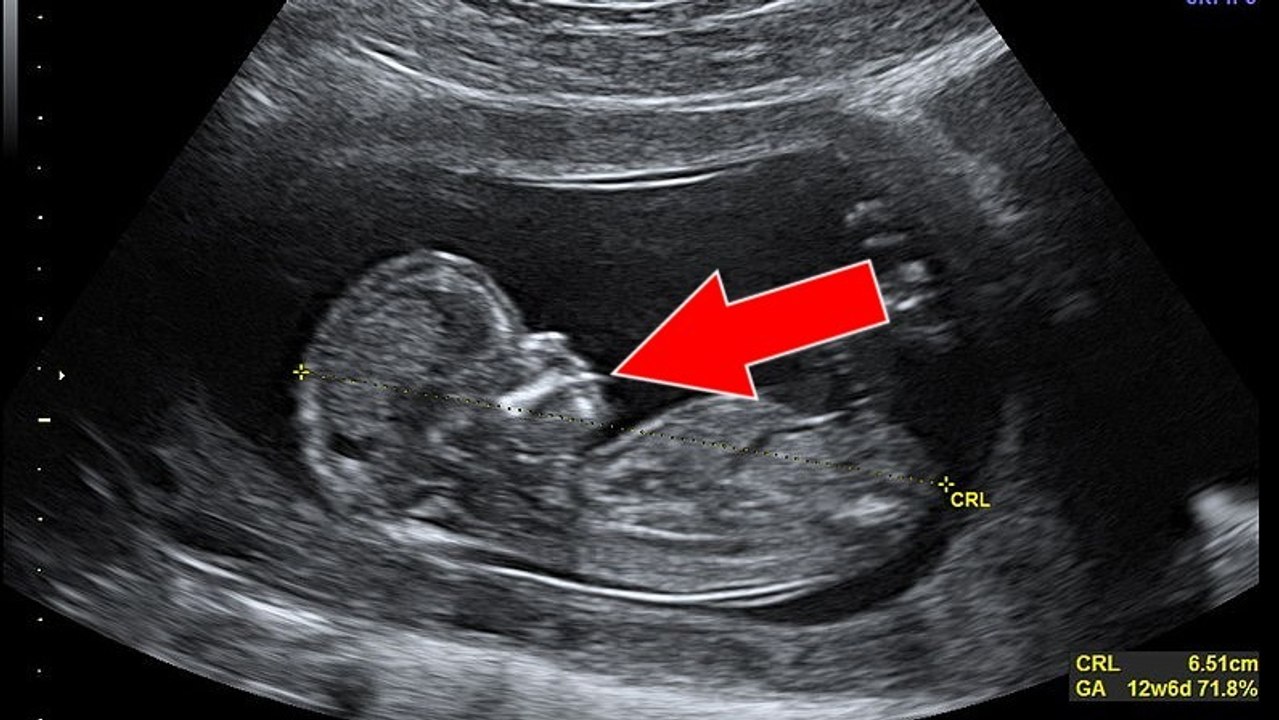

Cette femme a une grande surprise en assistant à l'échographie de sa soeur (vidéo)

Grossesse : ce médecin découvre une anomalie sur l'échographie de cette jeune femme 0:44